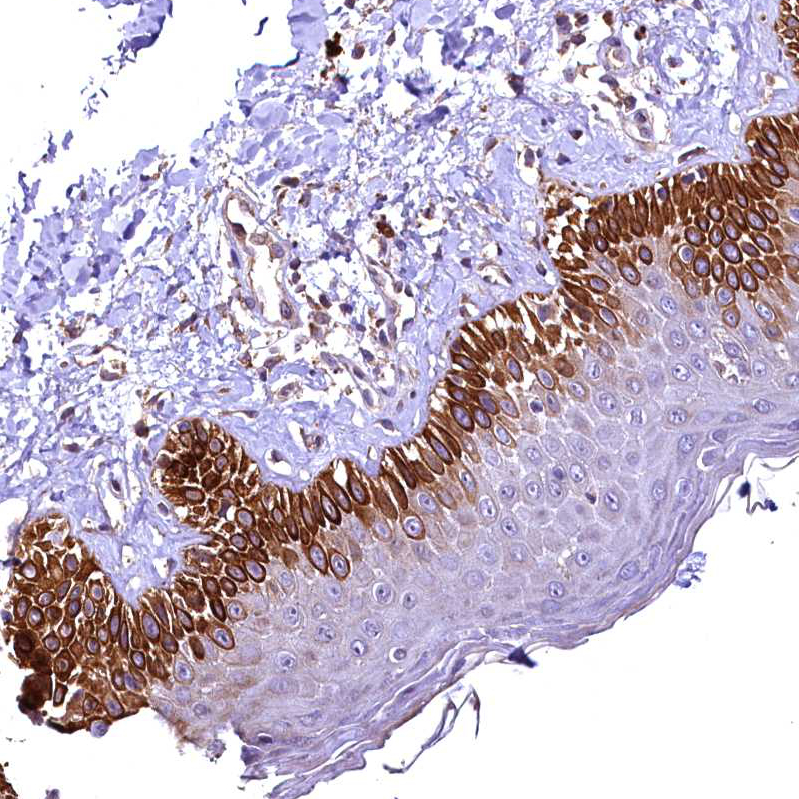

Immunohistochemical staining of human lung shows moderate cytoplasmic positivity in macrophages.